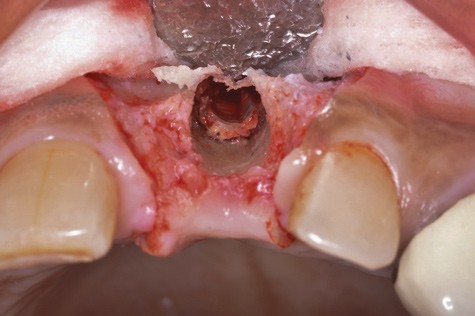

After gentle debridement with glycine air abrasion and sterile saline, a cross-linked, porcine collagen bone matrix (OSSIX® VOLUMAX; Datum Dental Ltd.) was placed over the buccal aspect of all three affected implants (Figure 17). Next, a subepithelial, connective tissue graft harvested from the right aspect of the patient's hard palate was affixed over the bone scaffold and exposed implants and abutments (Figure 18). And finally, a coronally advanced flap was sutured over the hard- and soft-tissue grafts. The 1-month, follow-up photograph demonstrates incomplete, but significant coverage of the previously exposed implants and abutments (Figure 19).

(19.) At 1-month postoperatively, partial coverage of the exposed abutments/implant platforms has occurred. There is now a band of keratinized mucosa, and the patient is instructed in nontraumatic plaque removal protocols. Follow-up to monitor long-term maintenance of the regenerated keratinized mucosa is encouraged.

Figure 19